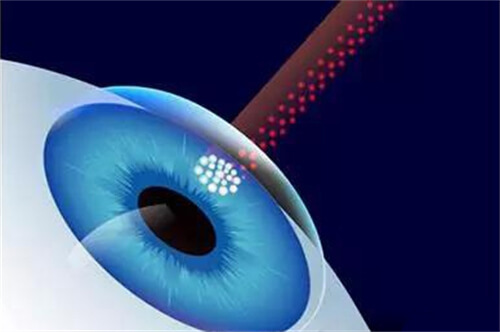

对于糖尿病视网膜病变患者,他创新性地结合抗VEGF药物注射与精密激光治疗,有效延缓病情进展。

孙医生团队特别重视围手术期视觉质量评估,运用微脉冲激光等新技术更大限度保护视功能。